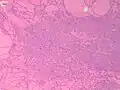

It can show hypercellular or microfollicular areas. There is no surrounding capsule (in contrast, a thyroid follicular adenoma or carcinoma is generally encapsulated). As shown in these microfollicles, it can have mildly enlarged nuclei with mildly clumped chromatin, and clear cytoplasms, but cellular characteristics of papillary thyroid carcinoma are absent.

As shown in these microfollicles, it can have mildly enlarged nuclei with mildly clumped chromatin, and clear cytoplasms, but cellular characteristics of papillary thyroid carcinoma are absent. Thyroid hyperplasia with a Sanderson polster, which is a group of small follicles that protrude into the lumen of a larger follicle. It should not be confused for papillary projections.

Thyroid hyperplasia with a Sanderson polster, which is a group of small follicles that protrude into the lumen of a larger follicle. It should not be confused for papillary projections. Various forms of degeneration are typically seen, with various forms pictured.

Various forms of degeneration are typically seen, with various forms pictured.